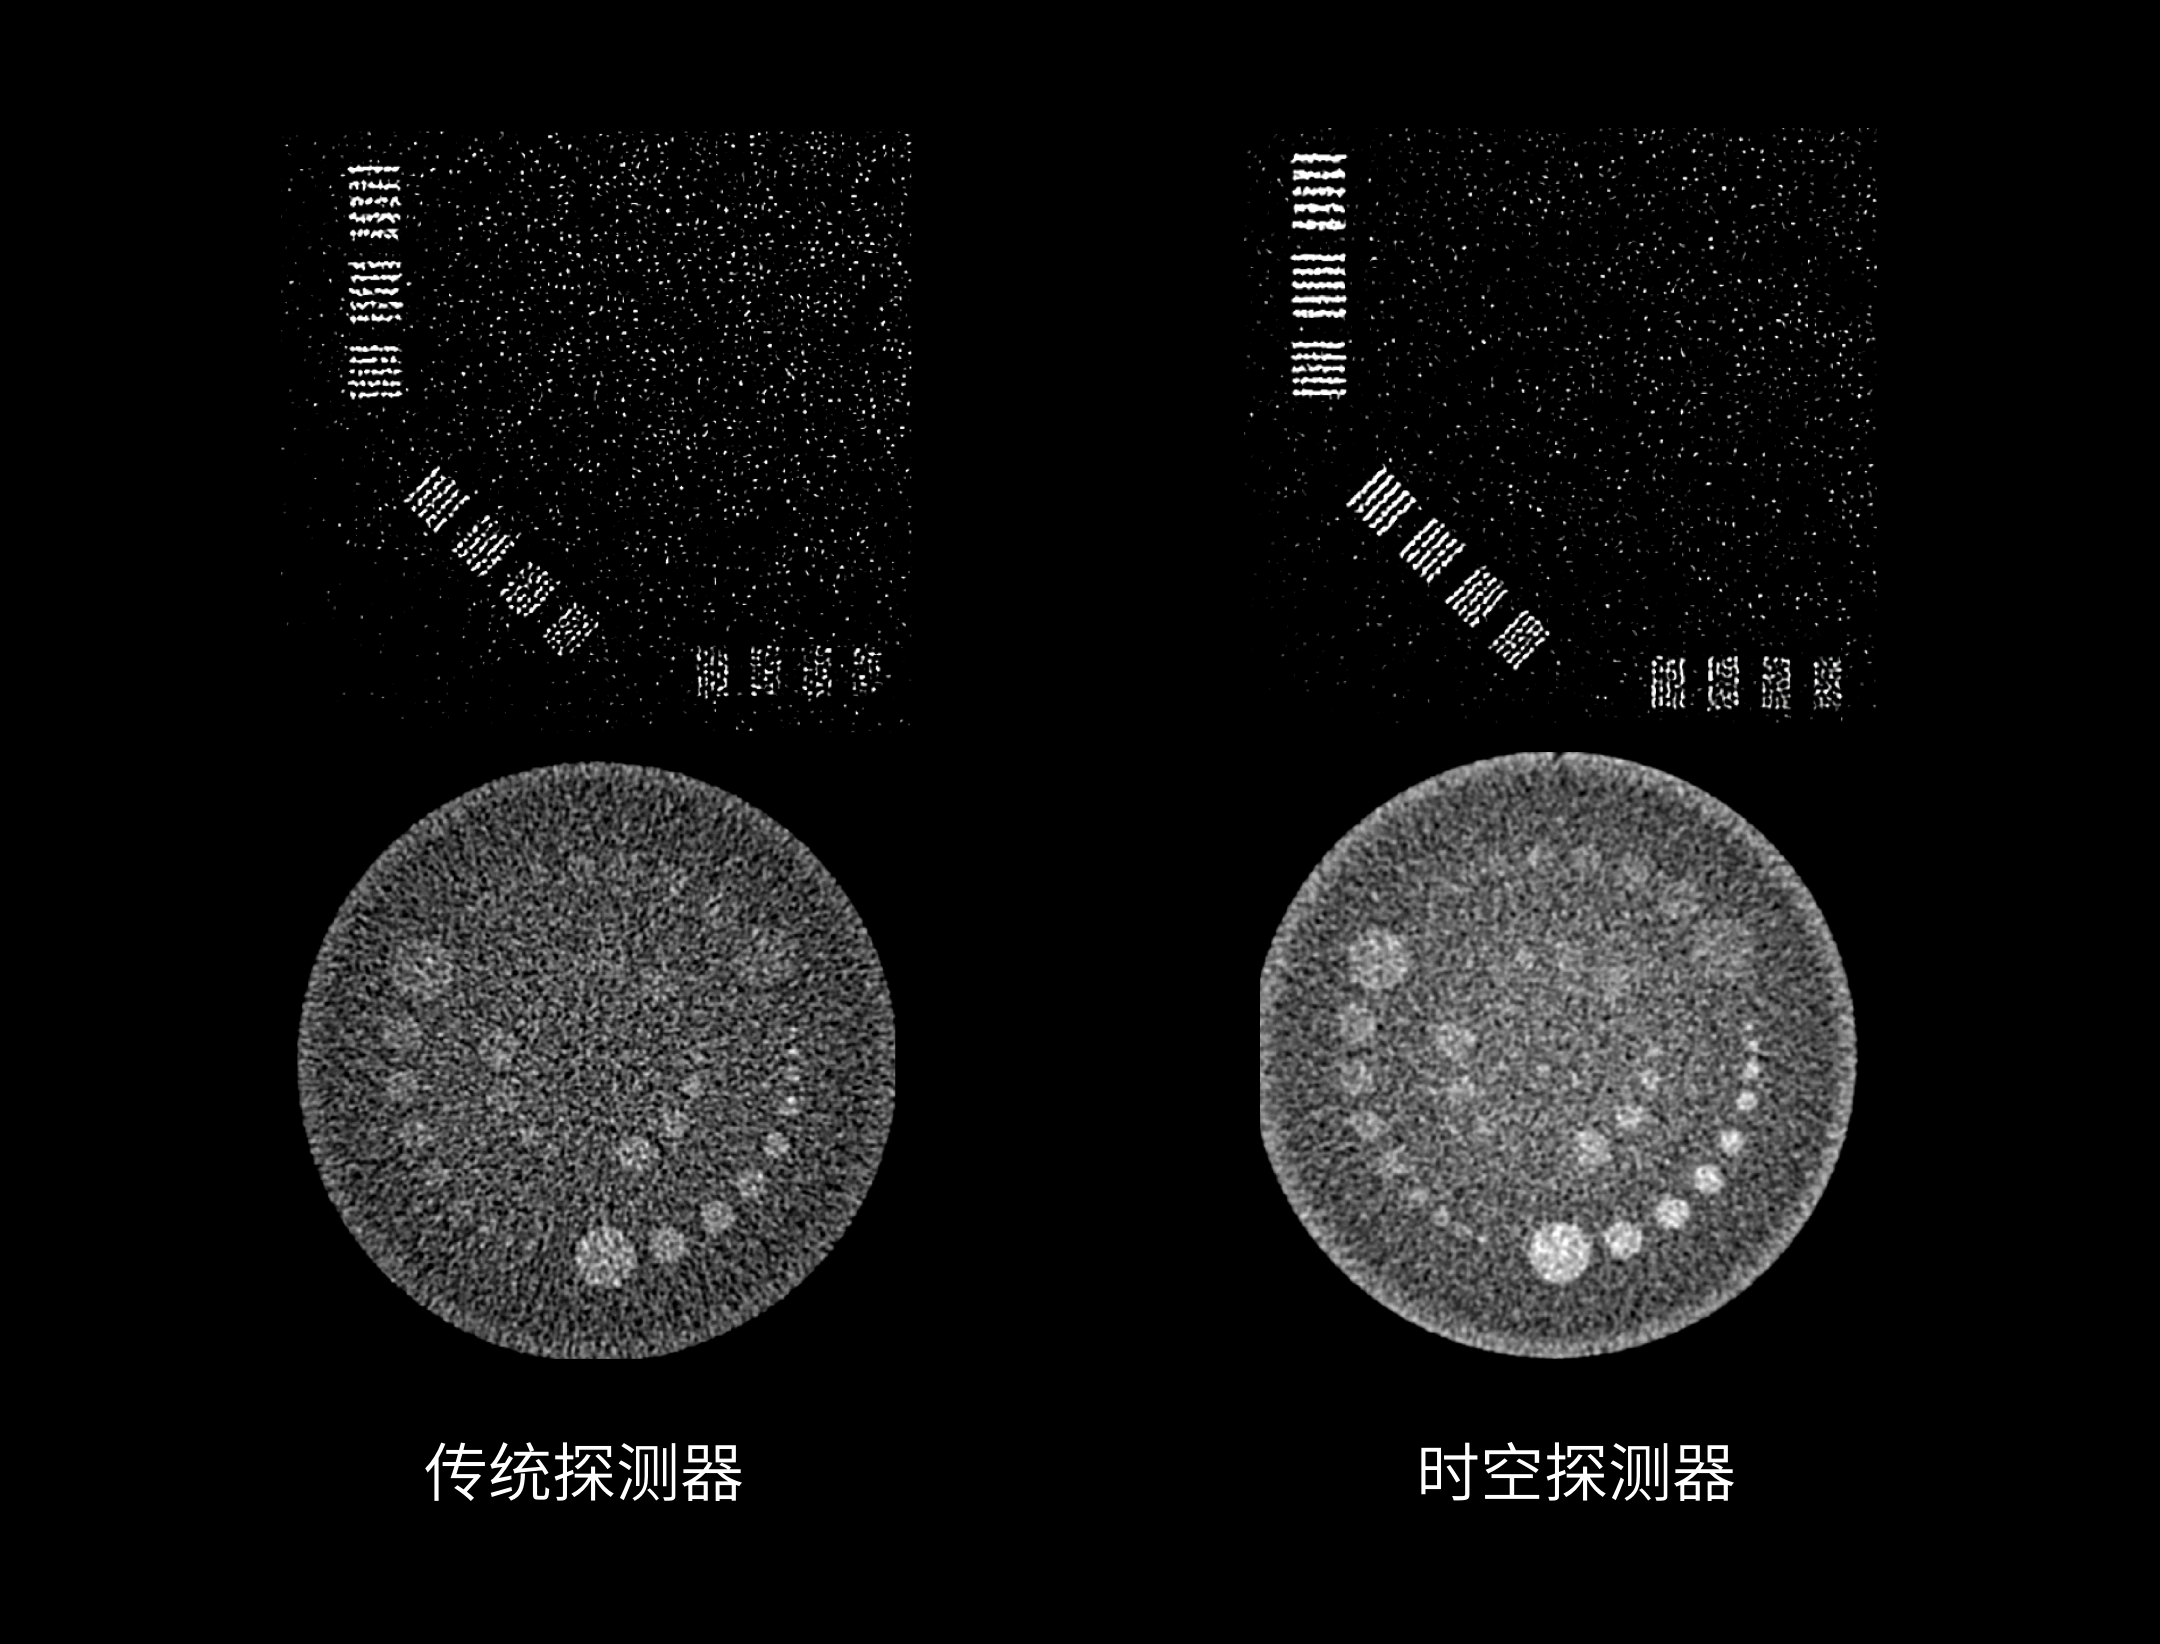

320层宽体时空探测器

0.5 mm 精细像素采集

0.5mm精细探测器单元尺寸,有效减少部分容积效应,显著提升图像空间分辨率。